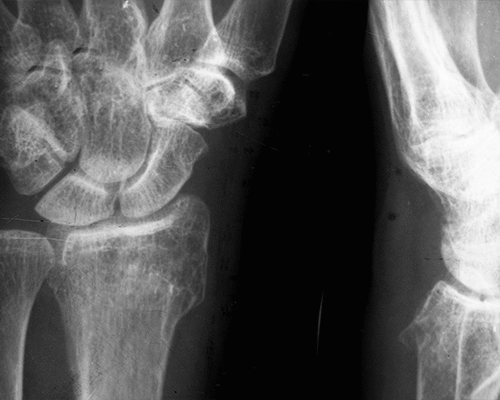

The use of bioresorbable magnesium (Mg)-based elastic stable intramedullary nails (ESIN) is highly promising for the treatment of pediatric long-bone fractures. Being fully resorbable, a removal surgery is not required, preventing repeated physical and psychological stress for the child. Further, the osteoconductive properties of the material support fracture healing. Nowadays, ESIN are exclusively implanted in a non-transphyseal manner to prevent growth discrepancies, although transphyseal implantation would often be required to guarantee optimized fracture stabilization. Here, we investigated the influence of trans-epiphyseally implanted Mg–Zinc (Zn)–Calcium (Ca) ESIN on the proximal tibial physis of juvenile sheep over a period of three years, until skeletal maturity was reached. We used the two alloying systems ZX10 (Mg-1Zn-0.3Ca, in wt%) and ZX00 (Mg-0.3Zn-0.4Ca, in wt%) for this study. To elaborate potential growth disturbances such as leg-length differences and axis deviations we used a combination of in vivo clinical computed tomography (cCT) and ex vivo micro CT (μCT), and also performed histology studies on the extracted bones to obtain information on the related tissue. Because there is a lack of long-term data regarding the degradation performance of magnesium-based implants, we used cCT and μCT data to evaluate the implant volume, gas volume and degradation rate of both alloying systems over a period of 148 weeks. We show that transepiphyseal implantation of Mg–Zn–Ca ESIN has no negative influence on the longitudinal bone growth in juvenile sheep, and that there is no axis deviation observed in all cases. We also illustrate that 95 % of the ESIN degraded over nearly three years, converging the time point of full resorption. We thus conclude that both, ZX10 and ZX00, constitute promising implant materials for the ESIN technique.

Elastic stable intramedullary nails (ESIN), Physis, Growth plate, Biodegradable implants, Mg–Zn–Ca, Sheep study, Long-term degradation behavior, ZX00, ZX10, Pediatric fracture treatment